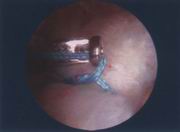

缝线穿过肩袖组织(图22)。

经工作套将缝线牵出关节外进行打结(图23)。